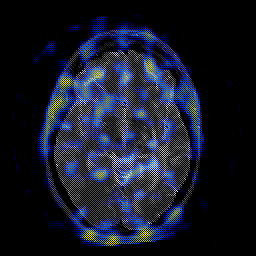

Glioblastoma multiforme overlay -- Slice #25

[Home][Help][Clinical][Tour 1][Tour 2][Tour 3] Slice 25